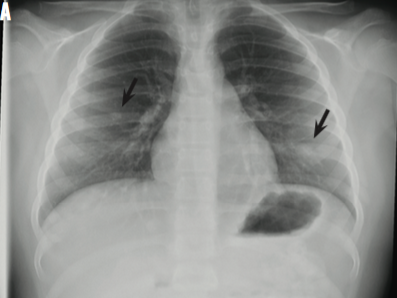

An 11-year-old boy presented with 6 days of a cough and right upper quadrant abdominal pain that radiated to the chest.